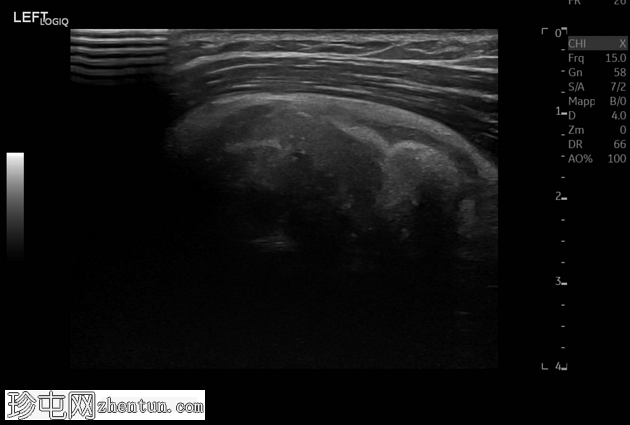

正位 -

可见肱骨头周围、三角肌腱和冈上肌腱之间有钙化沉积物,呈致密均匀的阴影。